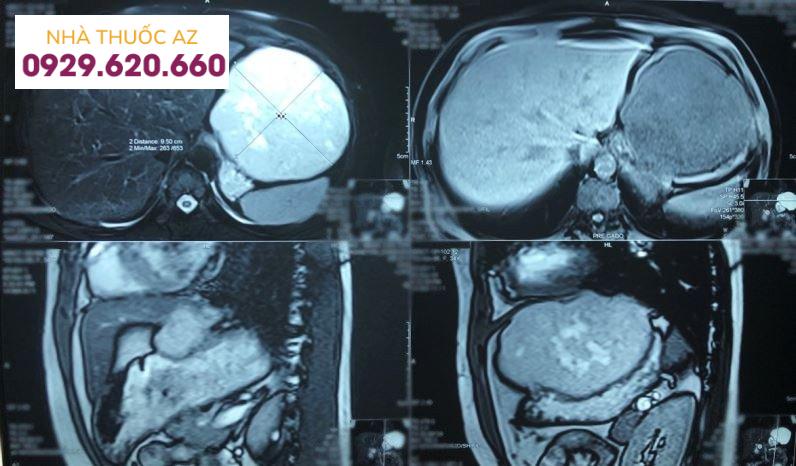

1.4 Chụp cộng hưởng từ gan

Chụp cộng hưởng từ (MRI) cho thấy u máu trong gan có sự xuất hiện điển hình là một tổn thương đồng nhất được phân định rõ ràng, giảm điểm trên ảnh trong thời kỳ T1 và T2.

Đồng thời, vì cả u máu hay u ác tính đều gây tăng âm trên hình ảnh T2W, sự phân biệt giữa hai tổn thương này được thực hiện bằng cách tăng thời gian dội âm: trong khi tín hiệu từ tổn thương ác tính có xu hướng giảm thì tín hiệu từ u máu trong gan lại tăng lên. Chính vì vậy, hình ảnh có trọng số khuếch tán cũng hữu ích trong việc phân biệt u máu trong gan với các tổn thương ác tính. Ngoài ra, chụp cộng hưởng từ gan với gadolinium có thể được sử dụng cho những bệnh nhân bị dị ứng với chất cản quang có iốt hoặc suy thận, những người chống chỉ định chụp CT.

Chụp cộng hưởng từ gan giúp xác định chính xác khối u máu trong gan